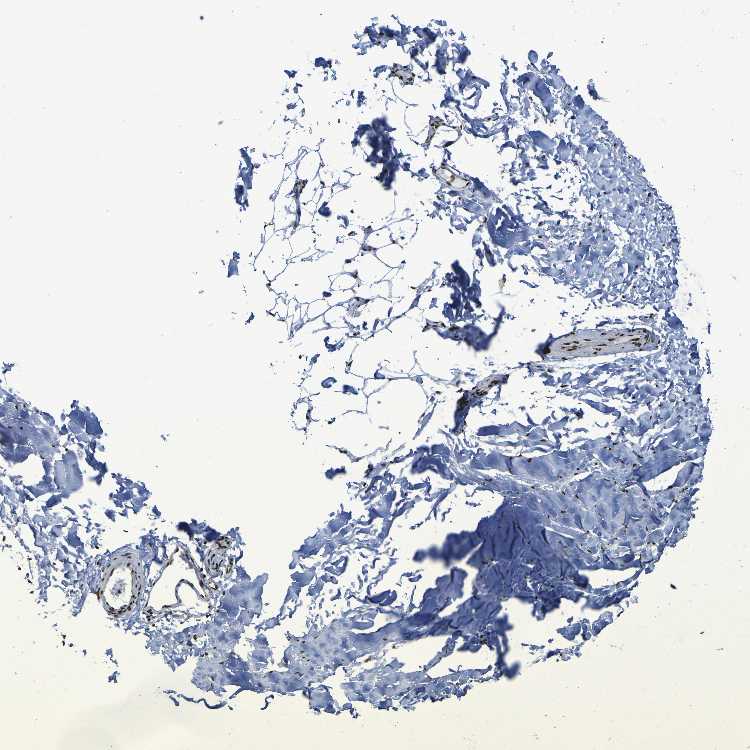

SOFT TISSUE 2 - Antibody stainingi

Antibody staining in the annotated cell types in the current human tissue is reported as not detected, low, medium, or high, based on conventional immunohistochemistry profiling in selected tissues. This score is based on the combination of the staining intensity and fraction of stained cells.

Each image is clickable and will lead to virtual microscopy that enables deeper exploration of all samples and also displays staining intensity scores, fraction scores and subcellular localization as well as patient and tissue information for each sample.

Antibody HPA026092Antibody CAB011687

Fibroblasts MediumHigh

Peripheral nerve LowMedium